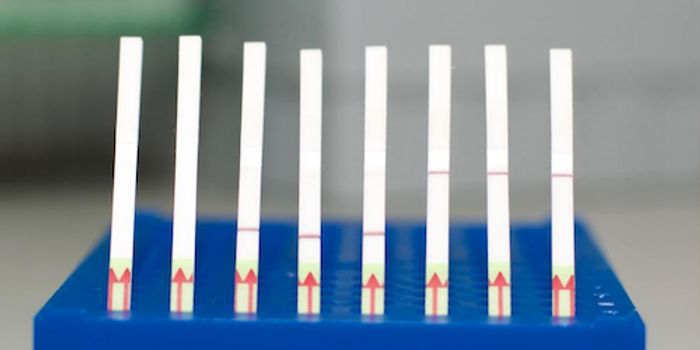

DEC 01, 2020Clinical & Molecular DXWidespread diagnostic testing capacities are an absolutely critical tool for countries battling the pandemic. For now, m ...